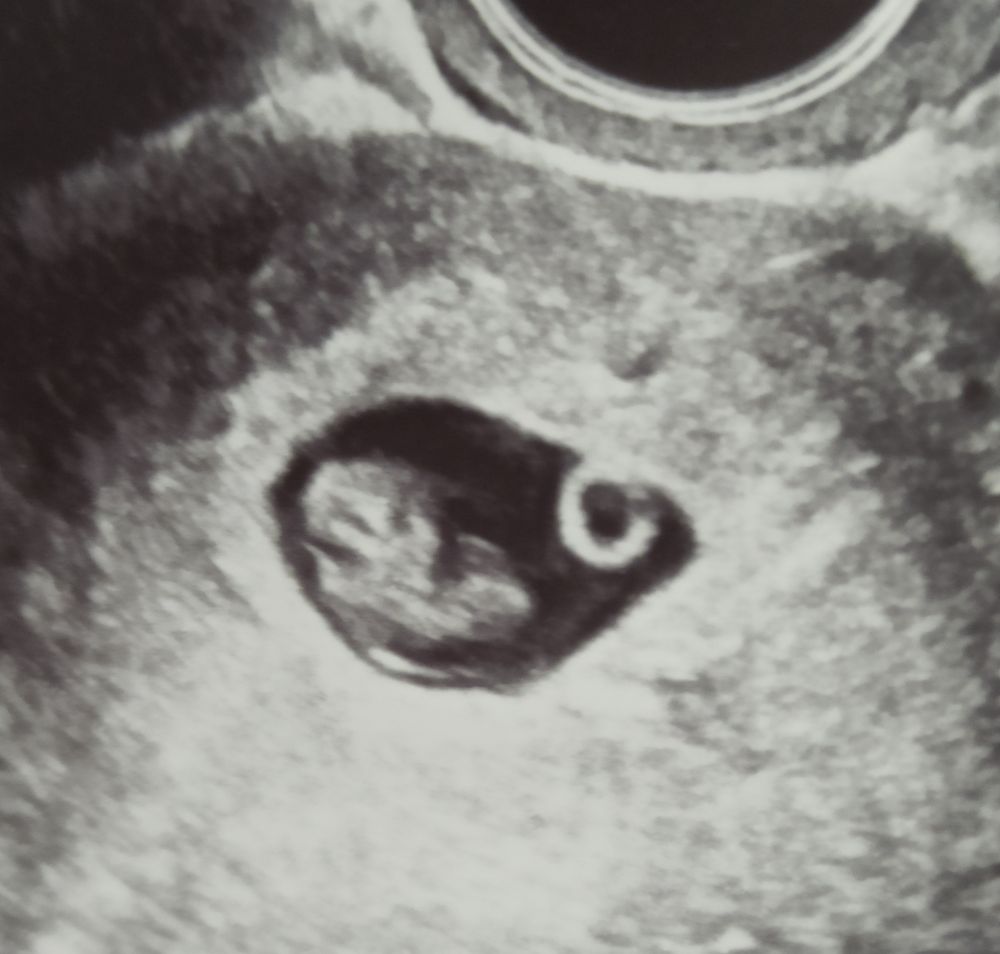

УЗИ на 41 дпо (7+6) ❤🤞🤞🤞

Сегодня 27 марта на 41 дпо (7+6) я сдала кровь в Инвитро на пол ребёнка, будет готов через 8 дней, где бы взять терпение, стараюсь не настраиваться на мальчика, чтобы не было сильно обидно. ХГЧ и прогестерон сдала для архива и сравнения с младшей дочкой, радует, что прогестерон стал чуть-чуть выше - 30,76 нг/мл, неделю назад был 26,74 нг/мл. По УЗИ всё хорошо слава Богу! 🙏🙏🙏 Киста ЖТ стала уменьшаться - 29*28 мм, неделю назад была 41*36 мм. Токсикоз так и не уходит, уже 3 недели мучаюсь, вымотана этой мутью, и ещё добавилась как 3-й день головная боль как мигрень, может от погоды, у нас ливень льëт 3-й день, слабость, головокружение, диарея сменилась запором, постоянно сушит во рту и горечь неприятная, от голода тошнит, после еды тяжесть и отрыжка. Хочу уже наконец-то наслаждаться беременностью, поскорей бы прошëл токсикоз.🙏🙏🙏